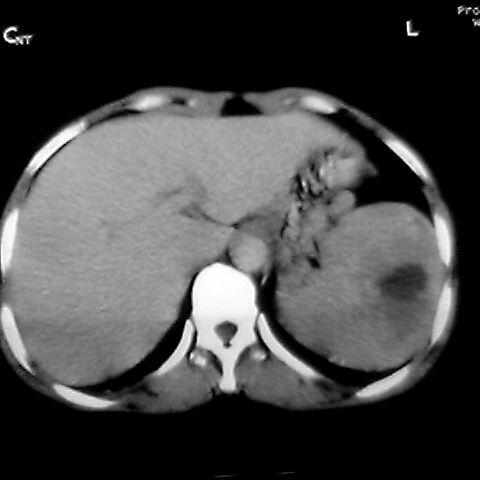

标题: [原创]CT4167脾占位。请大家帮忙会诊。

女 48岁 食道癌术前体检发现脾占位。

脾胀内部巨大低密度肿块,边界清或不清,中心坏死,轻度增强,内见散在钙化,结合食道癌病史多考虑:转移癌.

脾脏低密度灶伴钙化,增强化明显,中心见液化坏死灶,强化延时明显。考虑血管瘤。转移瘤待排。